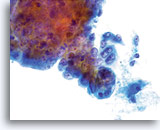

Glandulaire celclusters worden afgerond in PreservCyt-oplossing en kunnen uitschulpingen aan de randen van de groep vertonen. Let op de gladde, duidelijke cytoplasmische grenzen aan de rand van de groep.

40x